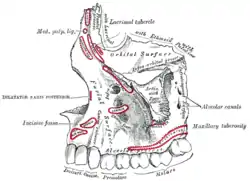

Mouth (oral cavity) Left maxilla, outer surface

Left maxilla, outer surface Base of skull, interior surface